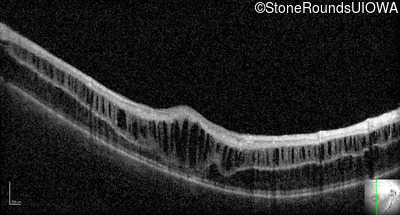

Optical Coherence Tomography - Right - 10/40

Exemplar / OCT Stack